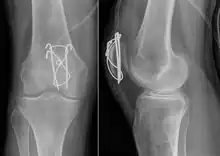

Tension band wiring: front and side view

Most patella fractures are transverse or comminuted, hence the quadriceps mechanism is disrupted and they are treated by a combination of wires in a tension band construct. This unites the fractured bones, reconstructing the straightening mechanism of the leg.[5][6]

If the patella is broken in several places, that is comminuted, then traditionally a patellectomy (removal of the whole patella) is performed in order to reconstruct the extensor mechanism and prevent the onset of an extension lag at the knee joint, resulting in instability.[5][8][9] Some surgeons however would rather opt for internal fixation.[8] A partial patellectomy is removal of only a portion of the patella, and may be carried out if at least 60% of the patella can be maintained.[6][8]